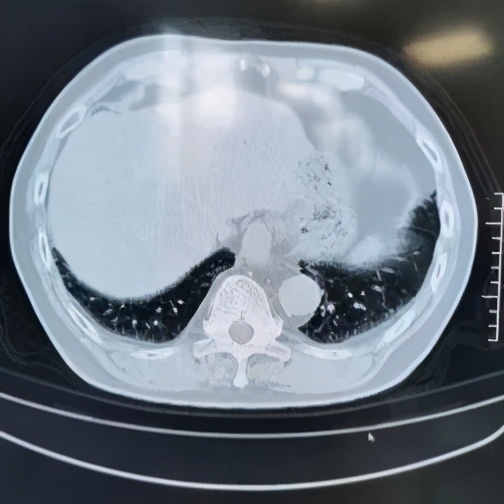

本院胸部CT(2019-08-30)示: 双肺弥漫性间质性改变,有网格状改变、毛玻璃影、局部有支气管牵拉形成支气管扩张的表现。

动脉血气(09-02):PaO2:68mmHg,PaCO2:35mmHg。动脉血气(09-11):PaO2:65mmHg,PaCO2:37mmHg。胸CT和肺功能都指向肺弥漫性间质性病变。

追溯患者2018年体检胸部CT(2018-1-22) :两肺下叶轻度间质增生,无显著双肺弥漫性间质改变。而且近一个月出现气促症状、低氧血症,说明间质性病变有活动性。